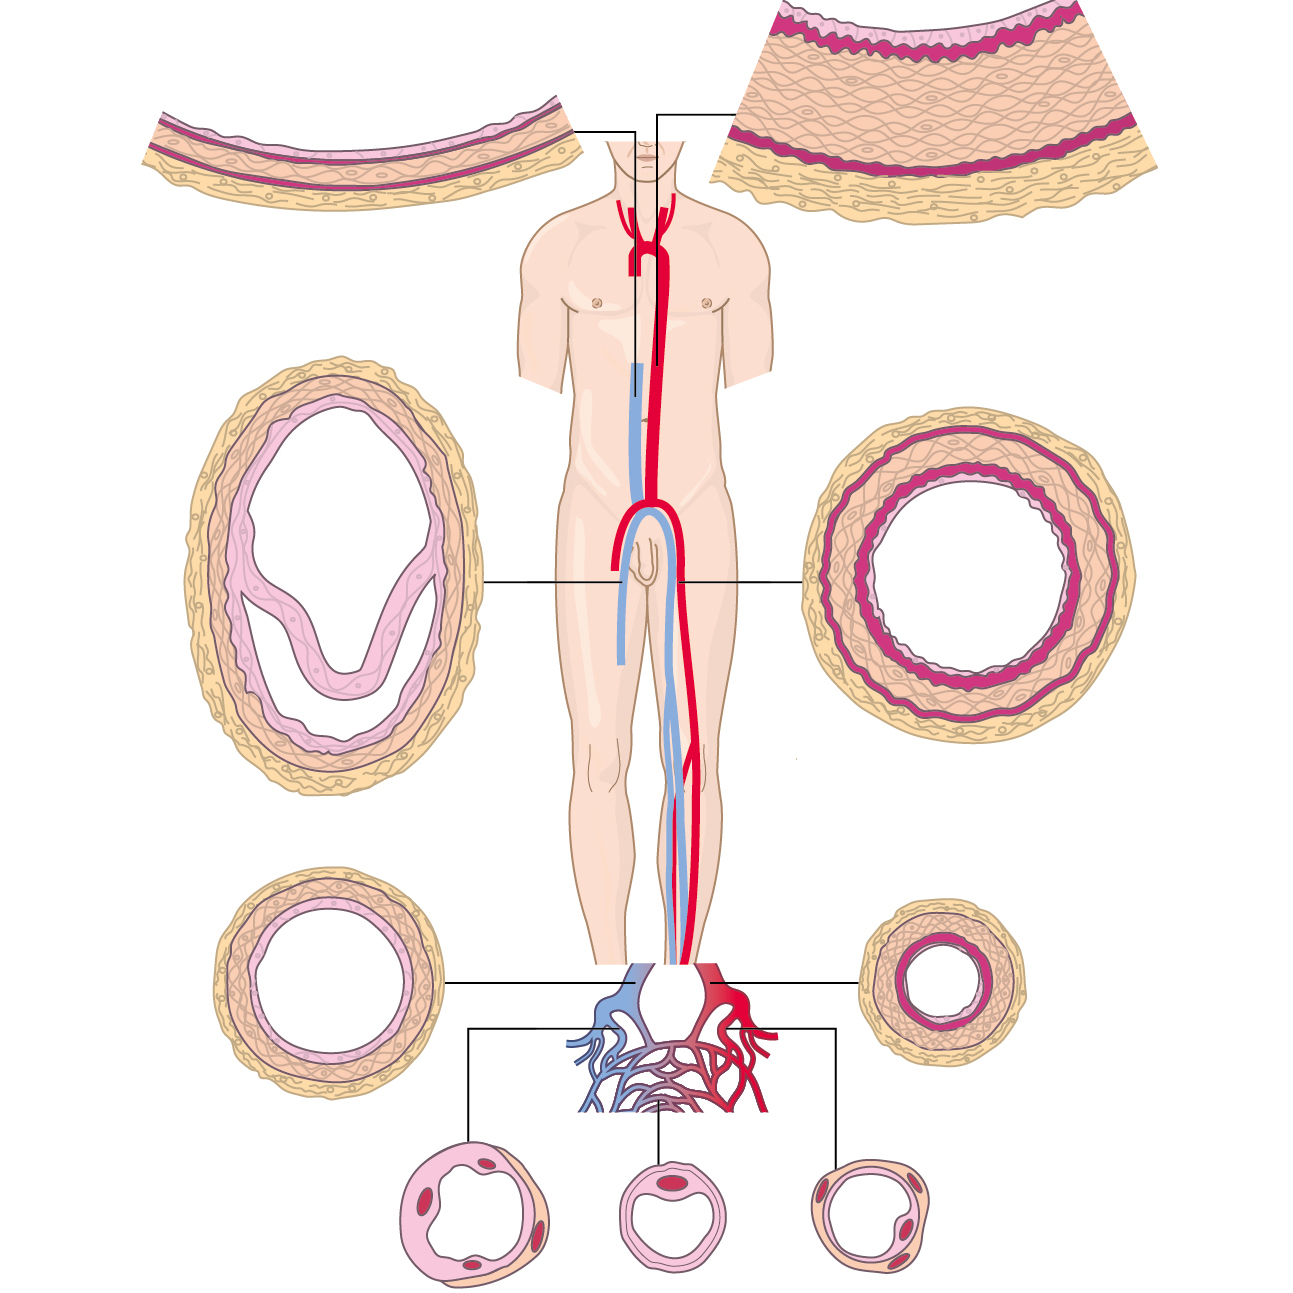

Medizinische Zeichnungen und Kinderbuch Illustration

Herzlich willkommen! Ich bin Ihre Expertin für medizinische Illustrationen und kreative Kinderbuch-Illustrationen. Mit einem Auge für wissenschaftliche Genauigkeit und einer Liebe zur Gestaltung kindgerechter Erzählwelten schaffe ich Bilder, die informieren und begeistern. Entdecken Sie mein Portfolio und lassen Sie sich von meiner Arbeit überzeugen!